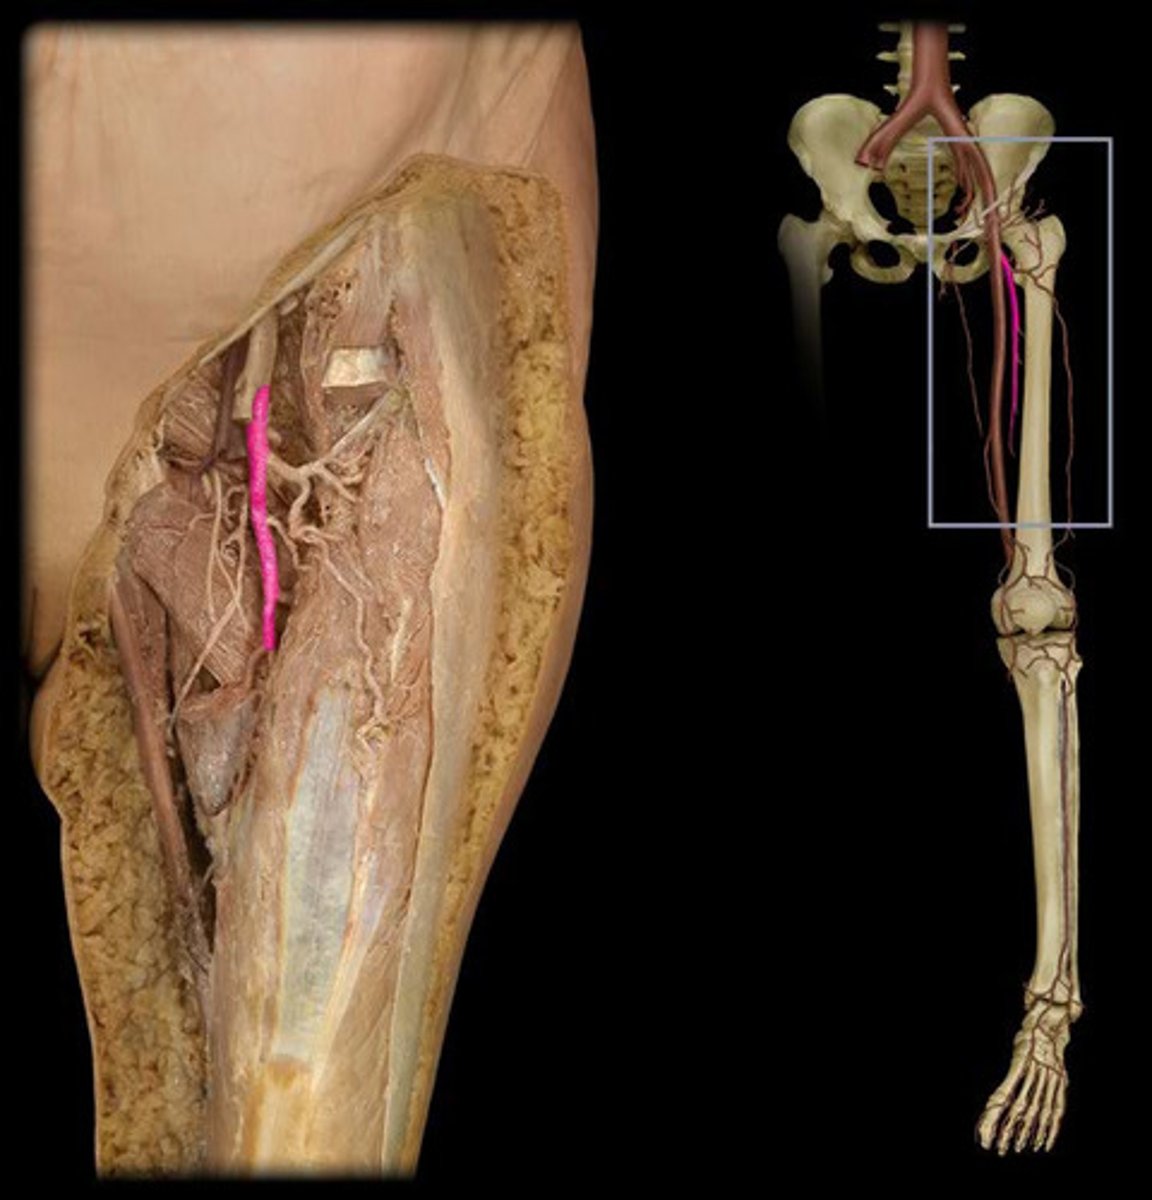

Right femoral artery